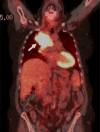

Case presentation: A 68-year-old female was diagnosed with stage IV non-small cell lung adenocarcinoma and was started on pembrolizumab. The patient developed sudden onset numbness and discoloration of fingertips bilaterally at week 25 after initiation of ICI treatment. Extensive workup to rule out hypercoagulable, autoimmune and vascular disease was unremarkable except for mild elevation of ANA and ESR. The symptoms quickly progressed into dry gangrene within four weeks and did not respond to medical or surgical treatment. Pembrolizumab was subsequently discontinued due to progression of metastatic disease. The patient refused further interventions and transitioned to hospice care where she expired after two months.